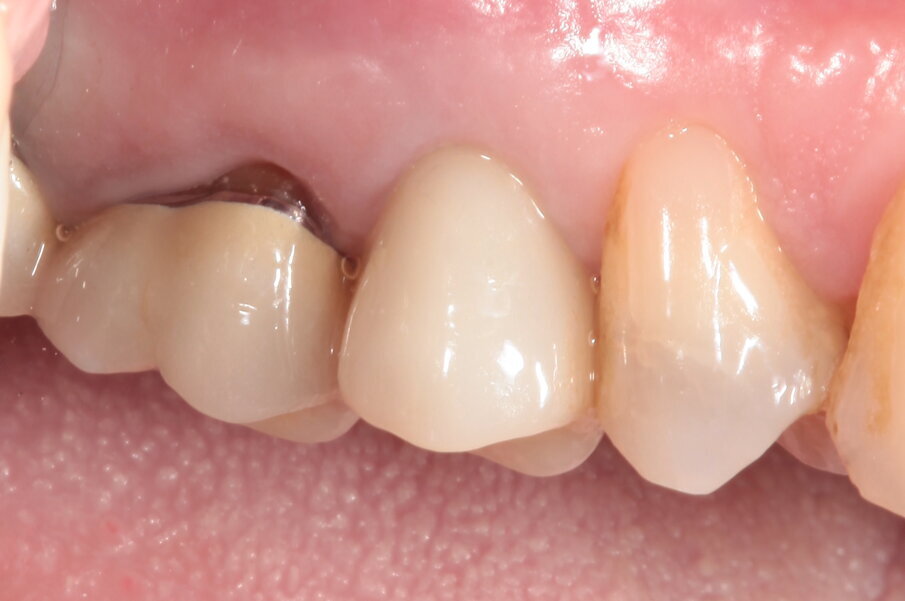

Nelle prime fasi questo avrà un profilo ovviamente non compatibile con quello di un restauro definitivo, ma molto utile per ottenere una compressione sul connettivo ormai maturo che migrerà verso vestibolare e verso coronale (Figg. 18-21). Dopo tre mesi, nei quali il provvisorio viene progressivamente ridotto nella sua componente vestibolare seguendo la risposta dei tessuti, e la paziente costantemente monitorata nel mantenimento della sua igiene orale, viene rilevata l’impronta tramite scanner ottico (Figg. 22-24) e consegnato il definitivo avvitato in zirconia, con un profilo ancora più ridotto e a questo punto ideale anche per il mantenimento igienico (Figg. 25-28).